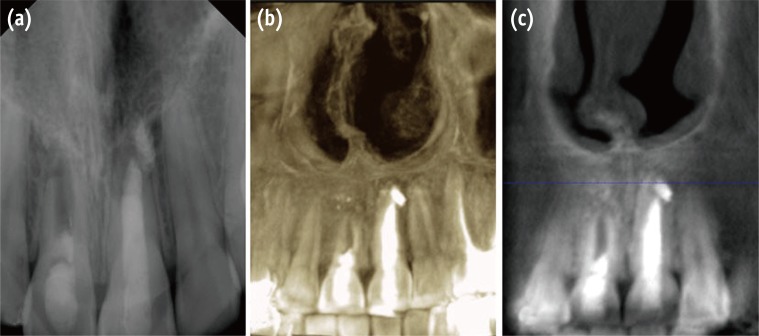

At 3 and 6 months follow-up, the patient was asymptomatic, and slight healing of the apical radiolucency was noticed (Figures 4a and 4b). The orthodontist was advised to use no force on the tooth. At the 12 months follow-up appointment, the patient remained asymptomatic, and the orthodontic appliances were removed. Radiographic examination demonstrated evidence of periradicular bone healing (Figure 4c). At the 3 year recall appointment, the patient was asymptomatic, and a periapical radiograph showed disappearance of the apical radiolucency and closure of the root apex (Figure 5a). The treatment outcome was confirmed with cone beam computed tomography (CBCT) images (Figures 5b and 5c).

In the case presented here, the radiographic and CBCT images demonstrated disappearance of periapical radiolucency and closure of the apical foramen without any significant increase in root length or root wall thickness. Similar findings have been reported previously.18,19,20,21 The periapical radiolucency usually disappears within 1 year of successful pulp revascularization,11,22,23,24 as was found in the present case. Healing of the periapical lesion after regenerative endodontic treatment has been demonstrated by Lenzi and Trope25 regardless of the absence of vital tissue inside the canal space. They attributed this to the disinfection protocol used during regenerative endodontic treatments. Closure of the apical foramen in immature teeth treated with regenerative endodontic procedures is achieved by growth of the periodontal ligament tissue as well as the deposition of cementum inside the canal space.26 In addition, Lin et al.27 and Shi et al.28 reported that the survival of postnatal dental pulp stem cells is facilitated by a rich apical blood supply at the open apex. These cells reside in the tissue of the dental pulp regardless of the status of the periapical tissue. The failure of root development was likely related to the previous trauma, persistent apical pathosis, poor endodontic management, and force applied in orthodontic treatment. It is believed that this causes the Hertwig epithelial root sheath, which is associated with root development, to lose its vitality.18,19,26,29,30 Chen et al.18 evaluated root developmental patterns with conventional radiographs. They reported that five types of root development pattern can occur as a result of regenerative endodontic procedures, all of which are based on survival of the Hertwig epithelial root sheath. The type 2 root development pattern, described as 'no significant continuation of root development with the root apex becoming blunt and closed', was seen radiographically and was confirmed with CBCT in the present case. This was achieved through good management of the failed treatment. Similar findings have been reported previously.19

Figure 4

Follow-up radiographs of tooth #11 at (a) 3 months; (b) 6 months; (c) 12 months.

Figure 5

Three year follow-up confirming the healing process. (a) Conventional radiograph; (b) CBCT three-dimensional reconstruction; (c) CBCT buccal view. CBCT, cone beam computed tomography.

Figure 4 Follow-up radiographs of tooth #11 at (a) 3 months; (b) 6 months; (c) 12 months.

Figure 5 Three year follow-up confirming the healing process. (a) Conventional radiograph; (b) CBCT three-dimensional reconstruction; (c) CBCT buccal view. CBCT, cone beam computed tomography.